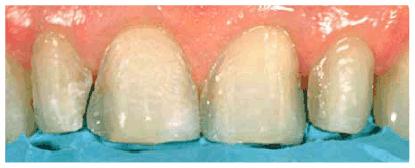

Figure

24-2C: After a slight reproportioning of the six anterior teeth, direct

composite resin was placed and contoured (6-mm ET [Brasseler,

Figure 24-2D: The final result shows improved proportion in tooth size and form.